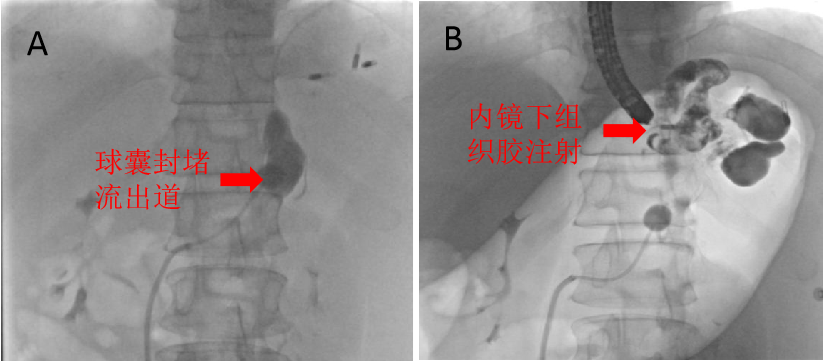

雪上加霜的是,患者门静脉CT血管造影术(CTA检查)示其除了胃静脉曲张还伴随着粗大的脾肾分流,这意味着针对胃静脉曲张出血普遍采取的手段——组织胶注射栓塞治疗,出现异位栓塞的风险将会显著增高,组织胶通过粗大的脾肾分流进入体循环,极易造成重要器官栓塞等严重并发症。

在介入中心导管室,肝胆介入科主任张跃伟带领廖勇、刘影医师,经右股静脉插管至脾肾分流道流出端,交换球囊随后顺利进入分流道,充盈的球囊成功阻断分流道,这一极易引发器官栓塞的“雷”被排掉了!

图片2.png

随后,消化科副主任任渝棠和陈涛医师在胃镜下穿刺胃底巨大曲张静脉,胃的蠕动、呼吸道起伏影响食管而导致的蠕动,双重加大操作的难度。在医生们默契的配合下,混有造影剂示踪的组织胶被打入了胃壁外曲张静脉,得益于球囊的阻断,组织胶未经过脾肾分流血管便进入了体循环,最终实现了胃底巨大曲张静脉的完全封堵。